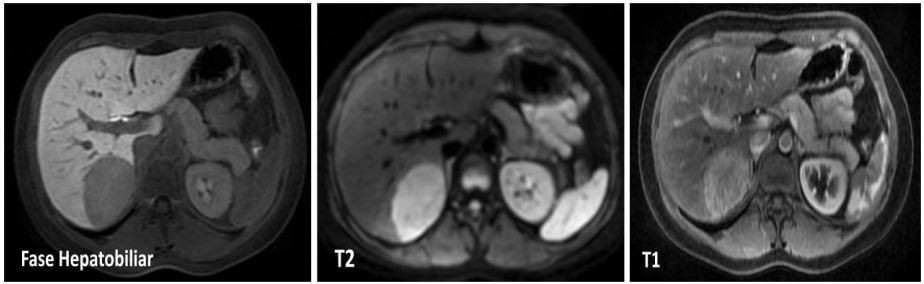

Homem, 42a, previamente hígido, inicia quadro dor abdominal, de leve intensidade, sem outros comemorativos. Realizou ultrassonografia de abdome com achado de lesão hipoecogênica, de 6cm, em segmento VI. Solicitada tomografia de abdome com achado de fígado sem sinais de hepatopatia e lesão homogênea, de limites bem definidos, medindo 4,9cm no maior eixo, localizada em segmento VI, com vascularização homogênea em fase portal sem cicatriz central, no entanto, não podendo descartar o diagnóstico de hiperplasia nodular focal.

Frente a este quadro, é solicitada ressonância magnética nuclear de abdome com contraste hepatobiliar especifico (PrimovistR ), com as seguintes imagens:

Qual o diagnóstico e a conduta?